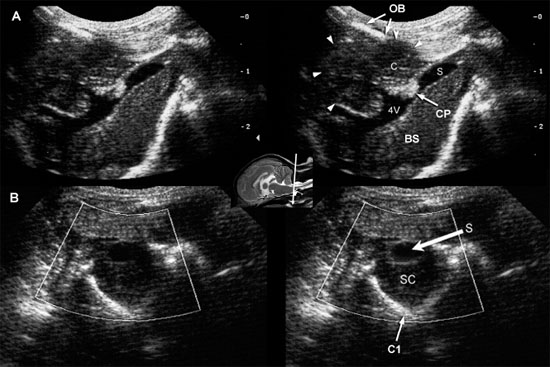

Chiari-like malformations are conditions in which there is variable pathology, such as malformation of the craniovertebral junction, cerebellar dysplasia, and elongation or displacement of portions of the cerebellum (Figure 1.20).

Herniation of the cerebellum can obstruct CSF flow, causing hydrocephalus and syringomyelia (Ettinger and Feldman 2005). Chiari type I malformations have been reported to occur in the Cavalier King Charles breed, with anomalies of the first cervical vertebra and skull, and in Maltese dogs (Kirberger et al. 1997). In some dogs, these conditions can be diagnosed by using the foramen magnum to provide an acoustic window in evaluating the cerebellum, fourth ventricle, spinal cord, and central canal.

Figure 1.20. Chiari-like malformation. Sagittal (A) and transverse (B) sonographic images obtained through a large foramen magnum in a dog with occipital dysplasia. The cerebellum (C, arrowheads) protrudes into the foramen, below the occipital bone (OB). A tubular anechoic fluid collection is observed along the middorsal portion of the cranial cervical spinal cord (SC), consistent with syringomyelia (S). The fourth ventricle (4V) is also dilated. Malformation of the skull enables better visualization of the brain than usual (compare with Figure 1.18). BS, brain stem; and CP, choroid plexus of the fourth ventricle. Images courtesy of M. A. d’Anjou.